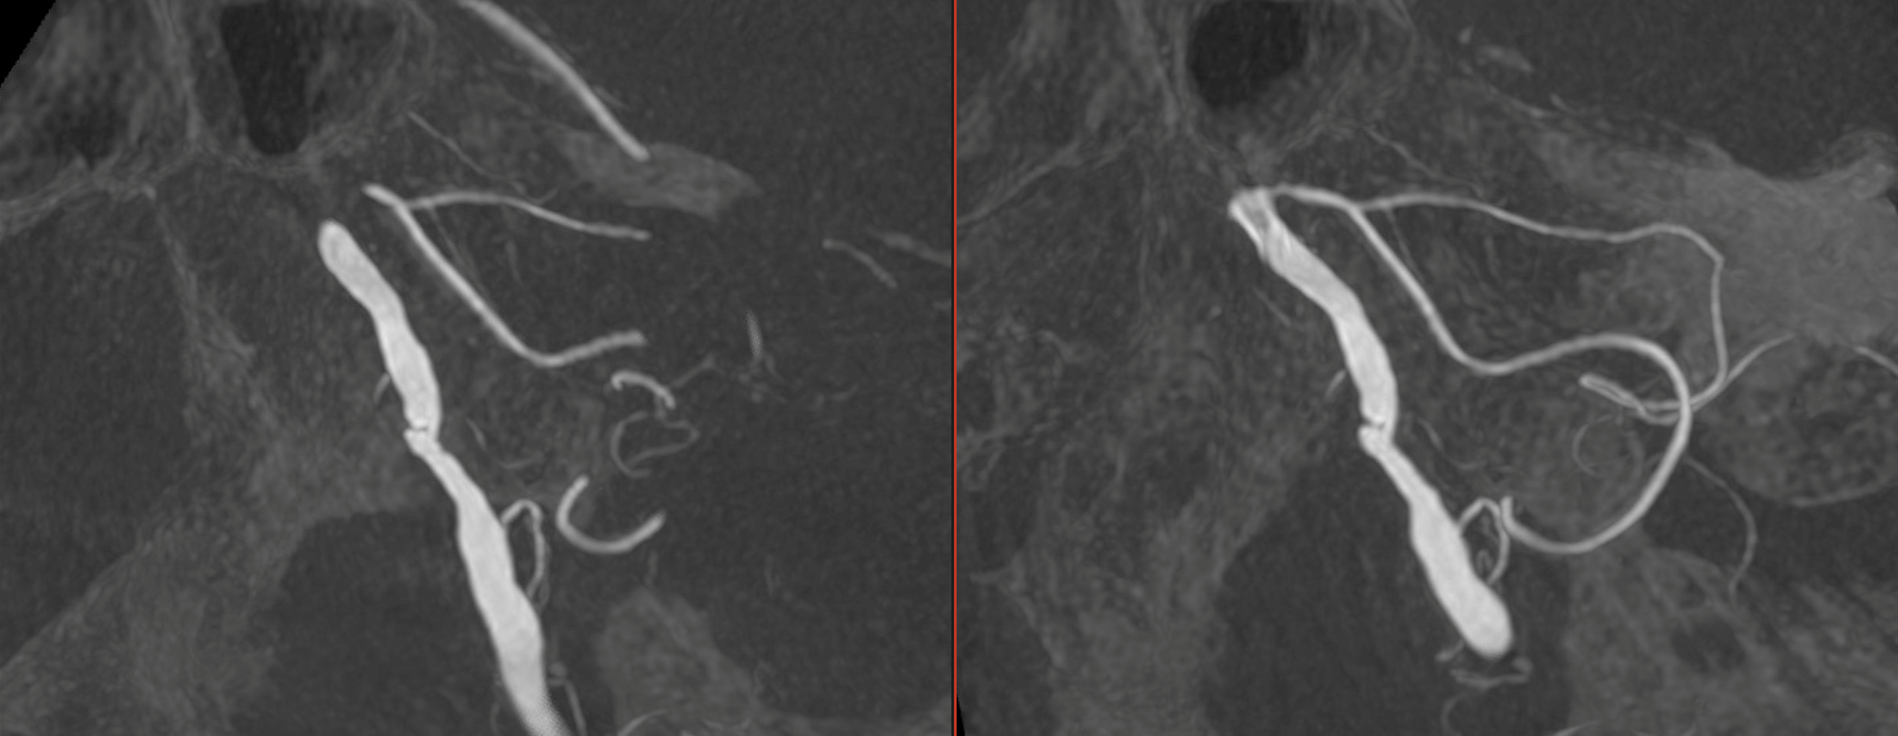

Thin MIP reconstructions of a 3D acquisition (5 seconds, 22 FOV, 20 ml pure contrast – 300 mg/ml – manual injection), confirming the stenosis, the AICA-PICA and the lateral spinal artery. (awake patient).